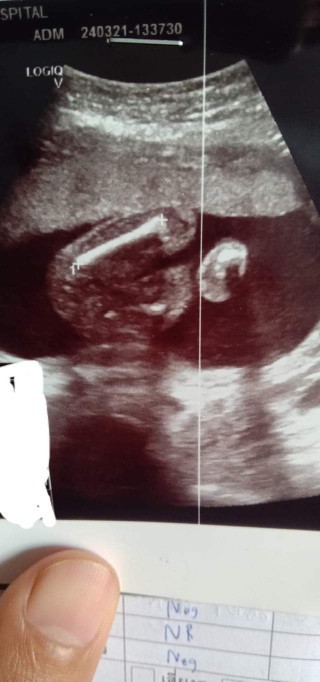

รูปตอนเค้าไปอัลตร้าซาวด์ค่ะ ที่หมอชี้เม้านั้นแหละค่ะจู๋ แหลมๆคล้ายๆของคุณแม่นะค่ะจากที่เค้าดูของคุณแม่

หน้าจะชายนะค่ะตรงขาวๆแหลมๆจู๋ป่าวค่ะ แหะๆ ดูไม่เป็นแต่แผ่นอัลตร้าซาวด์มีขาวๆแหลมๆเหมือนกันได้ชายค่ะ

ใบซาวน์นี้หมอบอกผู้หญิงค่ะ เพราะน้องมีร่องตรงที่โด่ออกมา แต่พอไปซาวน์อีกที่หมอบอกผู้ชายค่ะ ไม่รุ้จะเชื่อหมอไหนดีค่ะ แม่ งง และสับสนมาก

ชายค่ะของบ้านนี้ก็ชายชัดมากตรงลูกศรชี้มีอะจู๋แหลมๆ